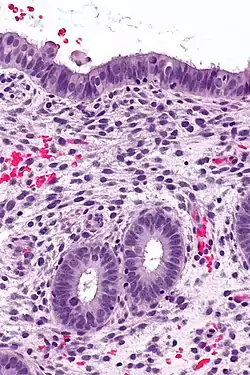

High magnification micrograph of decidualized endometrium due to exogenous progesterone (oral contraceptive pill). H&E stain

If there is inadequate stimulation of the lining, due to lack of hormones, the endometrium remains thin and inactive. In humans, this will result in amenorrhea, or the absence of a menstrual period. After menopause, the lining is often described as being atrophic. In contrast, endometrium that is chronically exposed to estrogens, but not to progesterone, may become hyperplastic. Long-term use of oral contraceptives with highly potent progestins can also induce endometrial atrophy.[13][14]